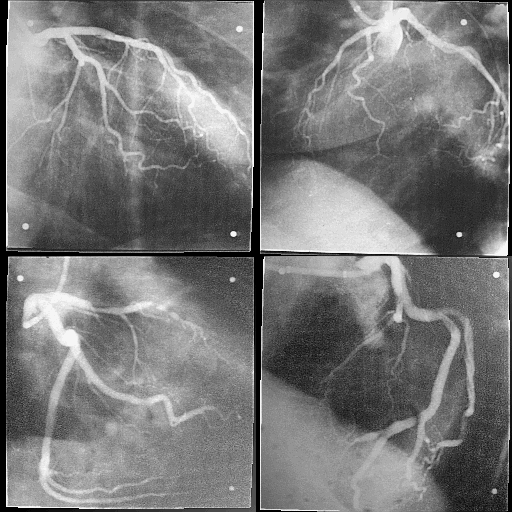

Coronary Artery Systems without and with Diffuse Disease